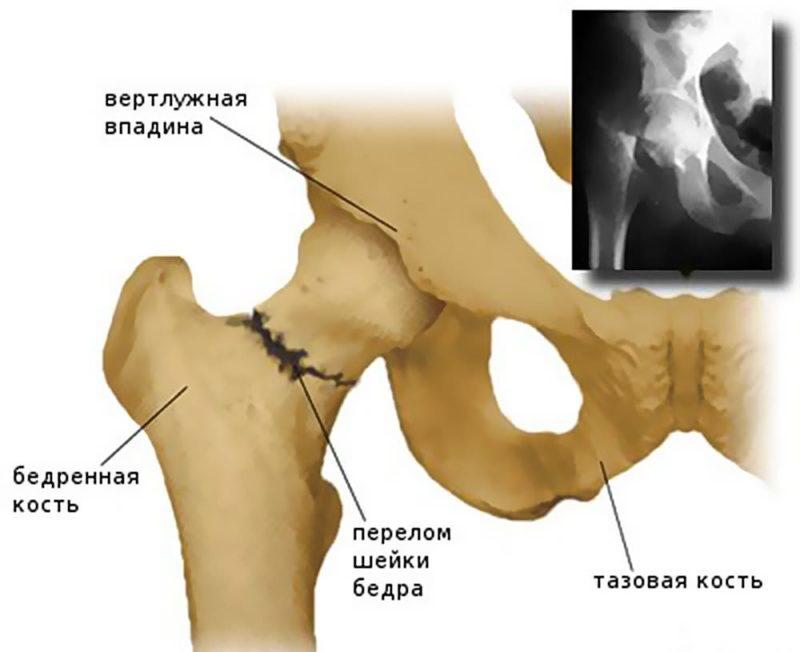

- шейки – повреждение локализуется в области сужения бедренной кости;

Наиболее информативным методом диагностики перелома является рентгенография. Рентгенографическое исследование выполняется в двух проекциях. В некоторых случаях может быть рекомендовано проведение компьютерной или магнитно-резонансной томографии.